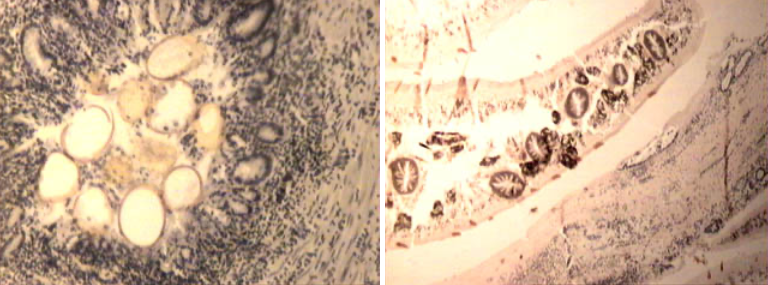

Fastsioloosne sapijuhapõletik

Koktsidioosne sapijuhapõletik

Maksa tsüstitserkoos